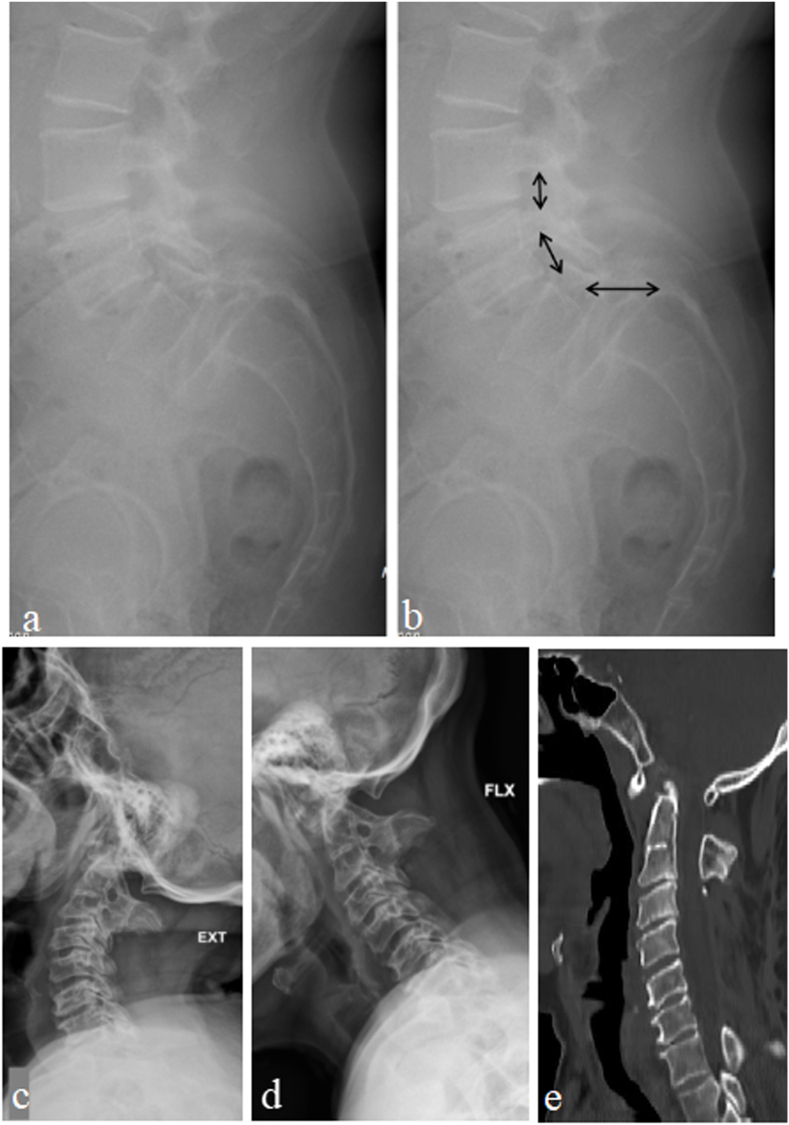

Fig. 6.

Case eg I: (a–b) Standing lateral radiograph of lumbar spine in a 50 years old female showing Grade III lytic Listhesis of L5 over S1. The arrow marks point to the attachment of ligamentum flavum in the interlaminar region. At L5-S1, the interlaminar region is widened causing stretch of ligamentum flavum due to the forward translation of L5 vertebra. Case eg II: (c–d) Dynamic Lateral cervical radiographs of a 30 years old male patient showing widening of Atlanto-Dens interval indicating instability at C1–C2; (e) Mid-sagittal and coronal CT scan image showing Atlanto-Occipital assimilation. Note that C1 posterior arch is small and is lying deep (patient has previously underwent cervical laminectomy) increasing the chances of cord injury during surgical exposure of C1–C2.

In patients with high grade spondylolisthesis, there will be widened interlaminar space (Fig. 6) with a stretched and taut ligamentum flavum. Hence, there is a high chance of dural injury during surgical exposure using electrocautery. Therefore, the use of electrocautery should be done only when the tip of the cautery rests over the bone and the subperiosteal dissection should be performed. Care must be taken while dissecting the soft tissues in the interlaminar region and it is better to use only cobb's elevator for muscle dissection over this space and avoid using electrocautery. Similarly in congenital disorders such as chiari malformation, complex spinal deformity patients with altered bony anatomy dural tears due to electrocautery are prone to occur. One of our patients with O–C junction anomaly had atlanto-occipital assimilation, which increased the chances of dural puncture with electrocautery during dissection (Fig. 6). In our study, six patients had a dural injury during exposure with electrocautery. One of our patients had a dural tear with endoscopic disc forceps while performing discectomy during endoscopic uniportal interlaminar lumbar decompression surgery. No repair of the tear was attempted as the tear was very small and tight skin closure was performed. In Minimally Invasive Spine (MIS) surgeries, the potential dead space for CSF accumulation is negligible as the muscle fibres overlap and fill in. Hence, the chances of dural leakage are significantly reduced. However, the literature has proponents for both repair14,15 and no repair16 following endoscopic dural injury. Heo et al., recently reported the application of non-penetrating titanium clips for dural repair in biportal endoscopic lumbar spine surgery. They concluded that clipping is an effective option for endoscopic dural repair without conversion to open microsurgery.17